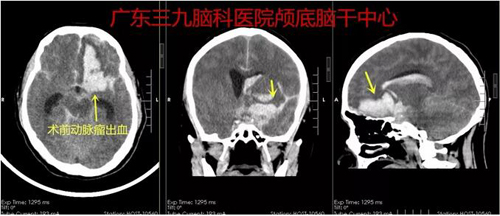

患者王某,男,49岁。因“突发头痛、呕吐伴意识不清1天余”于2018年10月28日入院。患者于26日晚饭后无明显诱因出现头痛,未行相关检查,于当地诊所输液治疗,具体不详,自诉稍好转。27日晚出现突发晕倒,伴多次呕吐,逐渐意识障碍,门诊查头颅CT示:左侧额颞叶脑出血并破入脑室、蛛网膜下腔出血,为进一步治疗转入广东三九脑科医院神经外一科,于28日行“大脑中动脉瘤夹闭术”,术程顺利,术后患者恢复好,对答切题,右侧肢体肌力4级,左侧肢体肌力5级。

▲图1:术前CT示广泛蛛网膜下腔出血,左侧额叶血肿形成